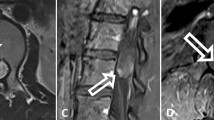

A 56-year-old woman was treated in this department for a C5–C6 spondylodiscitis. After 6 months her arms showed a rapid recovery, but her incomplete flaccid paraplegia remained stable. Magnetic resonance imaging (MRI) with gadolinium enhancement of the lumbar tract revealed an intramedullary lesion at the level of Th12–L1. During surgery, an intramedullary, poorly vascularized, dark gray lesion was detected and was totally removed. One year after surgery, no recurrence was encountered and the patient showed significant improvement.